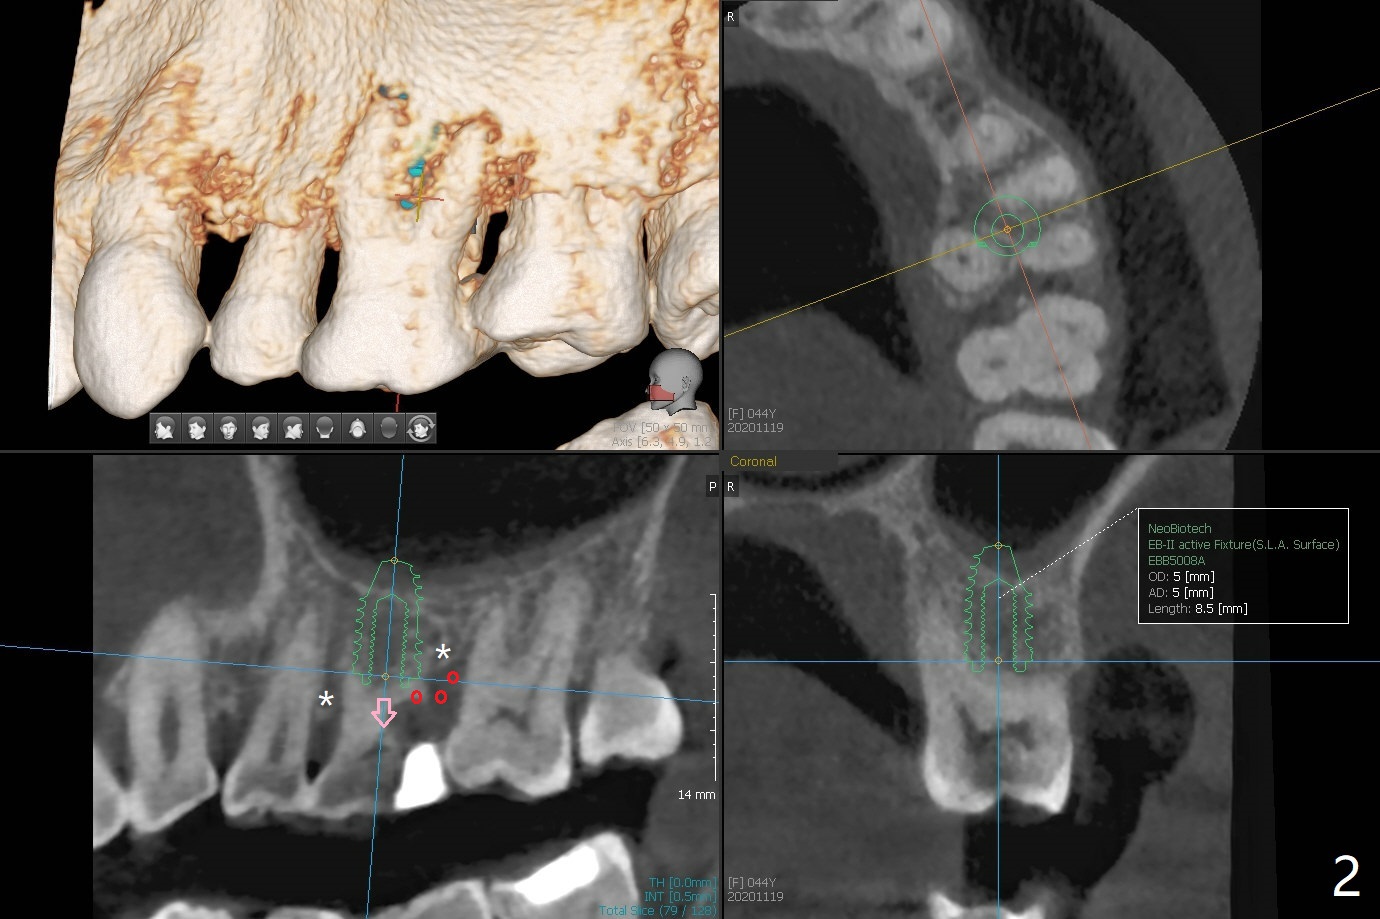

44岁女左上6远中深龋(图一:*),同意拔除种植(图二),由于近中,远中牙槽嵴不等(*),为了增加冠根比例,植体可以种浅些(箭头),但是远中多放置骨粉(红色)。为了防止钻头偏移中隔,去除牙冠(图三),保留牙根情况下,完成钻洞(图四:红色),然后拔除牙根(图五:黑色),放置植体(绿色)。